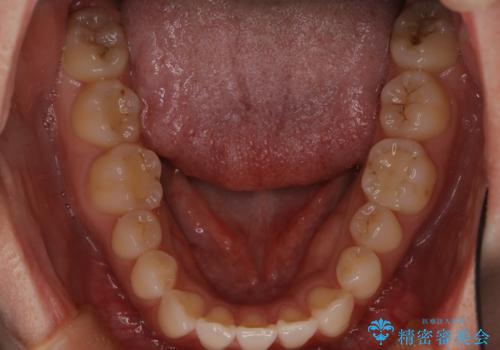

- 八重歯と、右上前歯(2番)が下の歯より内側に入っている反対咬合を気にされてご来院されました。精密な検査の結果、八重歯と反対咬合を同時に改善するためには、歯列全体にスペースを確保する必要があると判明。患者様のご希望から、透明で目立たないインビザライン(マウスピース矯正)による治療計画を立案しました。奥歯全体を奥へ動かす遠心移動でスペースを作り、これらの複雑な問題を一括で解消することを目指します。

今回の矯正治療では、透明なマウスピース型の装置インビザラインを使用しました。治療は、緻密なデジタル計画に基づき、奥歯から順に歯列全体を後方へ移動させる遠心移動を実施。これにより、八重歯を正しい位置に並べるためのスペースを確保しました。同時に、右上の2番を前方に誘導することで反対咬合を解消。結果として、抜歯することなく八重歯と反対咬合という複数の問題が改善され、機能的で美しい歯並びを獲得していただけました。